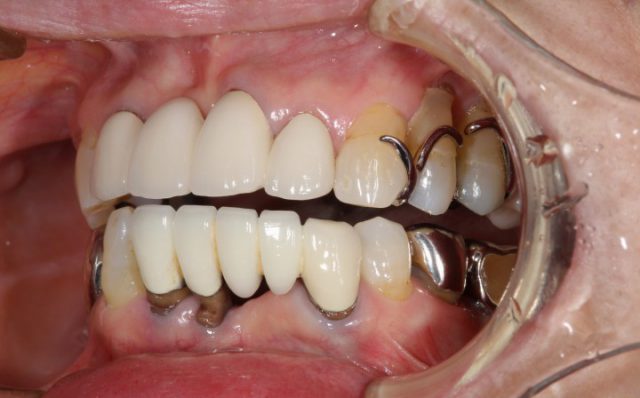

施術前

施術後

下がってきた歯茎にあわせるように新しい被せ物をつけていくので、術前に比べるととても自然です。今回の患者さまのように欠損している歯をブリッジにより回復する場合にはメタルボンドのような土台を金属でつなげたほうが強度が出ます。

上の歯を治療して以来、逆に下の歯がとても目立ってしまっていたと気になされていた患者さまですが、術後の仕上がりをみてとても喜んでおられました。